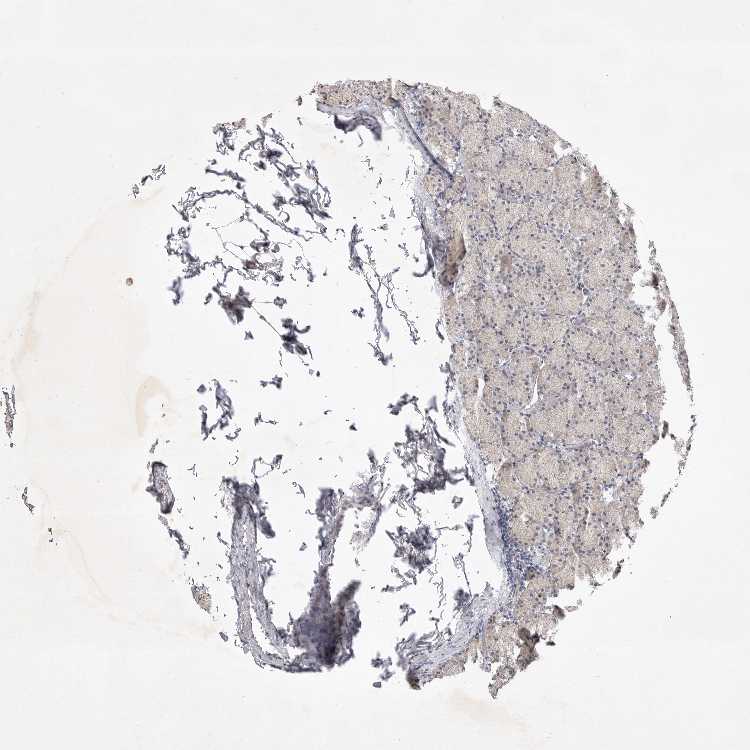

STOMACH 1 - Antibody stainingi

Antibody staining in the annotated cell types in the current human tissue is reported as not detected, low, medium, or high, based on conventional immunohistochemistry profiling in selected tissues. This score is based on the combination of the staining intensity and fraction of stained cells.

Each image is clickable and will lead to virtual microscopy that enables deeper exploration of all samples and also displays staining intensity scores, fraction scores and subcellular localization as well as patient and tissue information for each sample.

Antibody HPA026786

Glandular cells Not detected